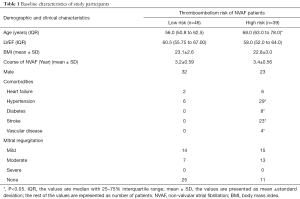

Clinical characteristics

Clinical characteristics of the thromboembolism high- and low-risk groups are shown in Table 1. There were no significant differences in LVEF, body mass index (BMI), or the clinical course of NVAF between the 2 groups. The high-risk group had higher numbers of participants with hypertension, diabetes, stroke, and vascular disease than the low-risk group, but the differences in sex, heart failure, and mitral regurgitation between the 2 groups were not significant. Also, compared to the low-risk group, the high-risk group was more advanced in age.

Full table